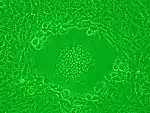

Syncytia can also form when cells are infected with certain types of viruses, notably HSV-1, HIV, MeV, SARS-CoV-2, and pneumoviruses, e.g. respiratory syncytial virus (RSV). These syncytial formations create distinctive cytopathic effects when seen in permissive cells. Because many cells fuse together, syncytia are also known as multinucleated cells, giant cells, or polykaryocytes.[12] During infection, viral fusion proteins used by the virus to enter the cell are transported to the cell surface, where they can cause the host cell membrane to fuse with neighboring cells.